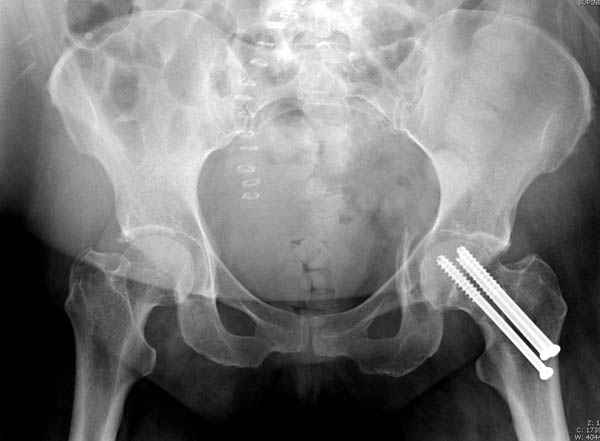

Перелом шейки смогли зафиксировать через пару дней, ацетабулум до сих пор не оперирован, на вытяжении.

Из-за упущенного времени (три недели с момента

поступления) ацетабулум ведем консервативно.

На снимке ацетабулума редко встречающийся очень низкий перелом, наверное, трудно было репозицию через один доступ? Перелом как бы замкнулся в квадрилатеральной поврехности.